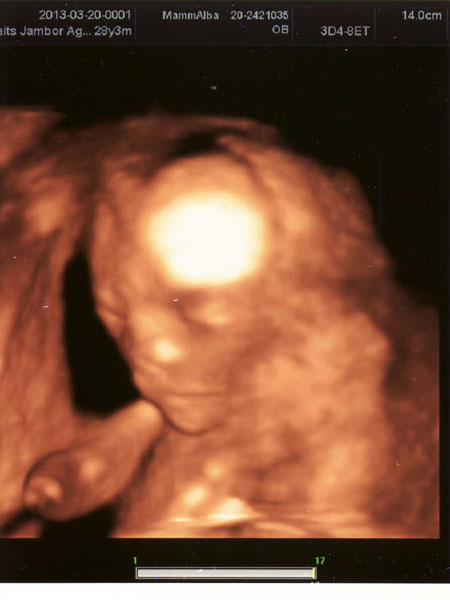

igen megnyugodtam picit, holnap elmegyünk egy 4d-re